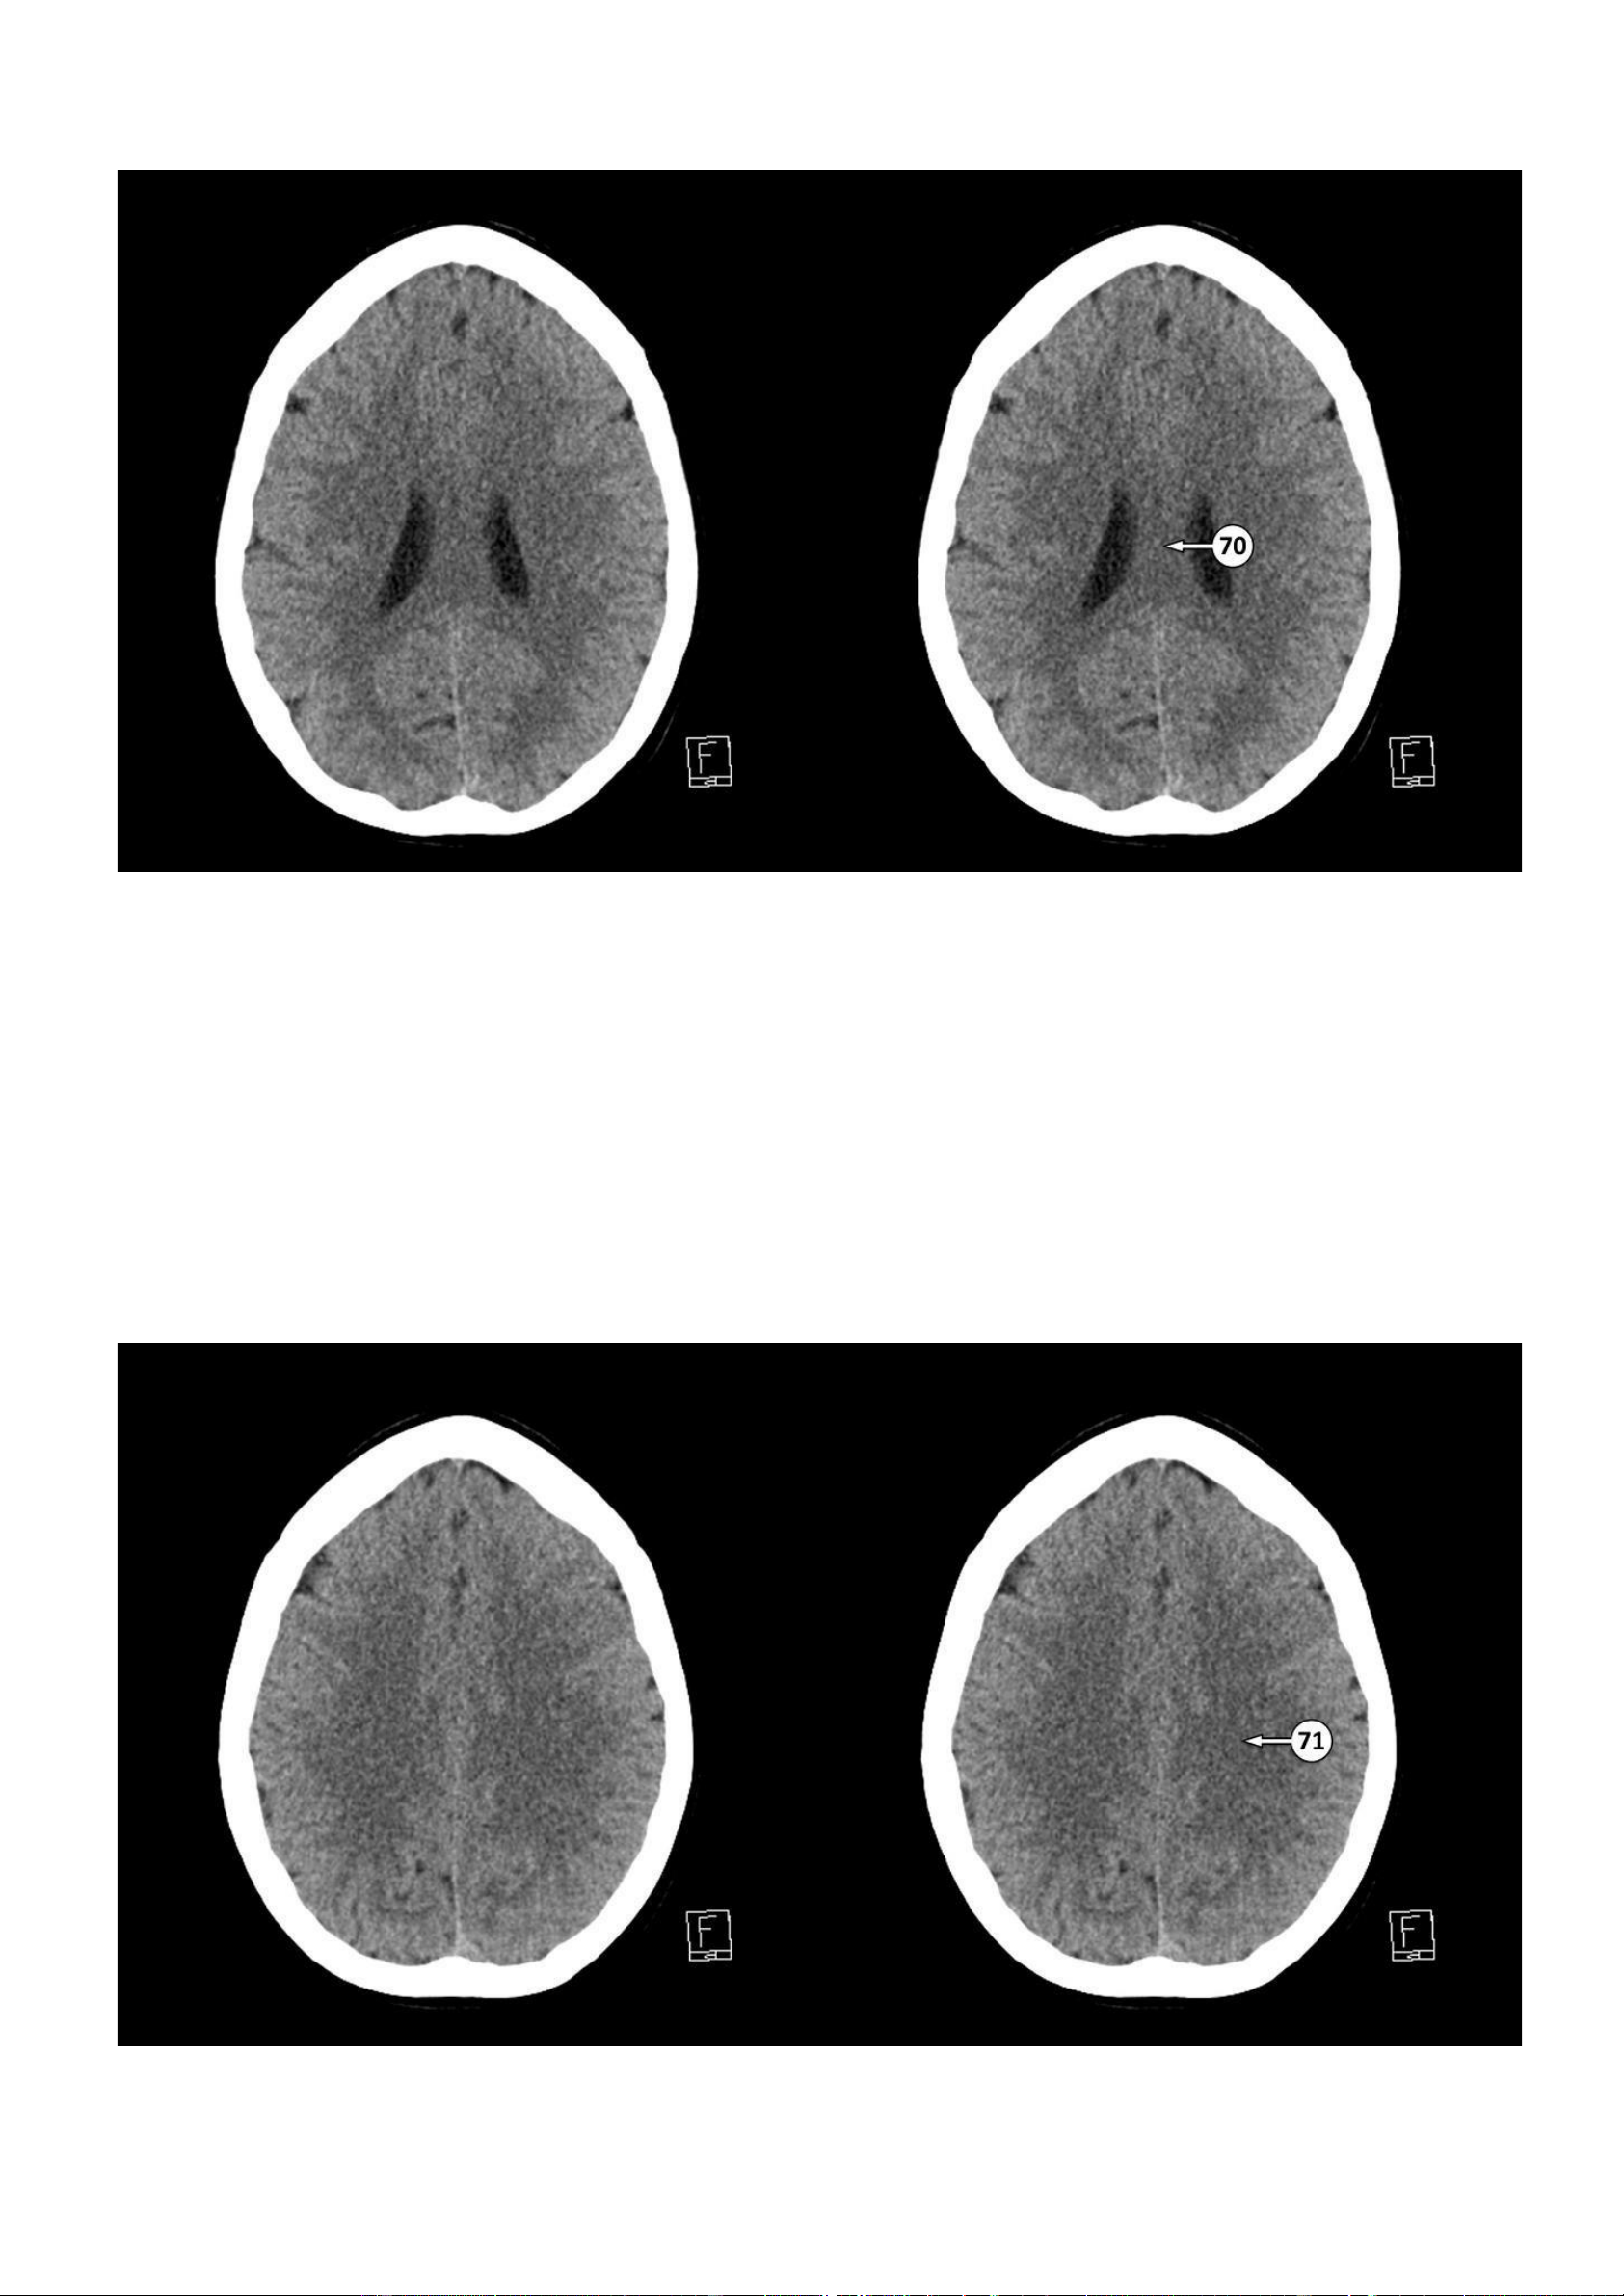

▪ Số 70: Thân của thể chai

71: Trung tâm bán bầu dục lOMoAR cPSD| 22014077